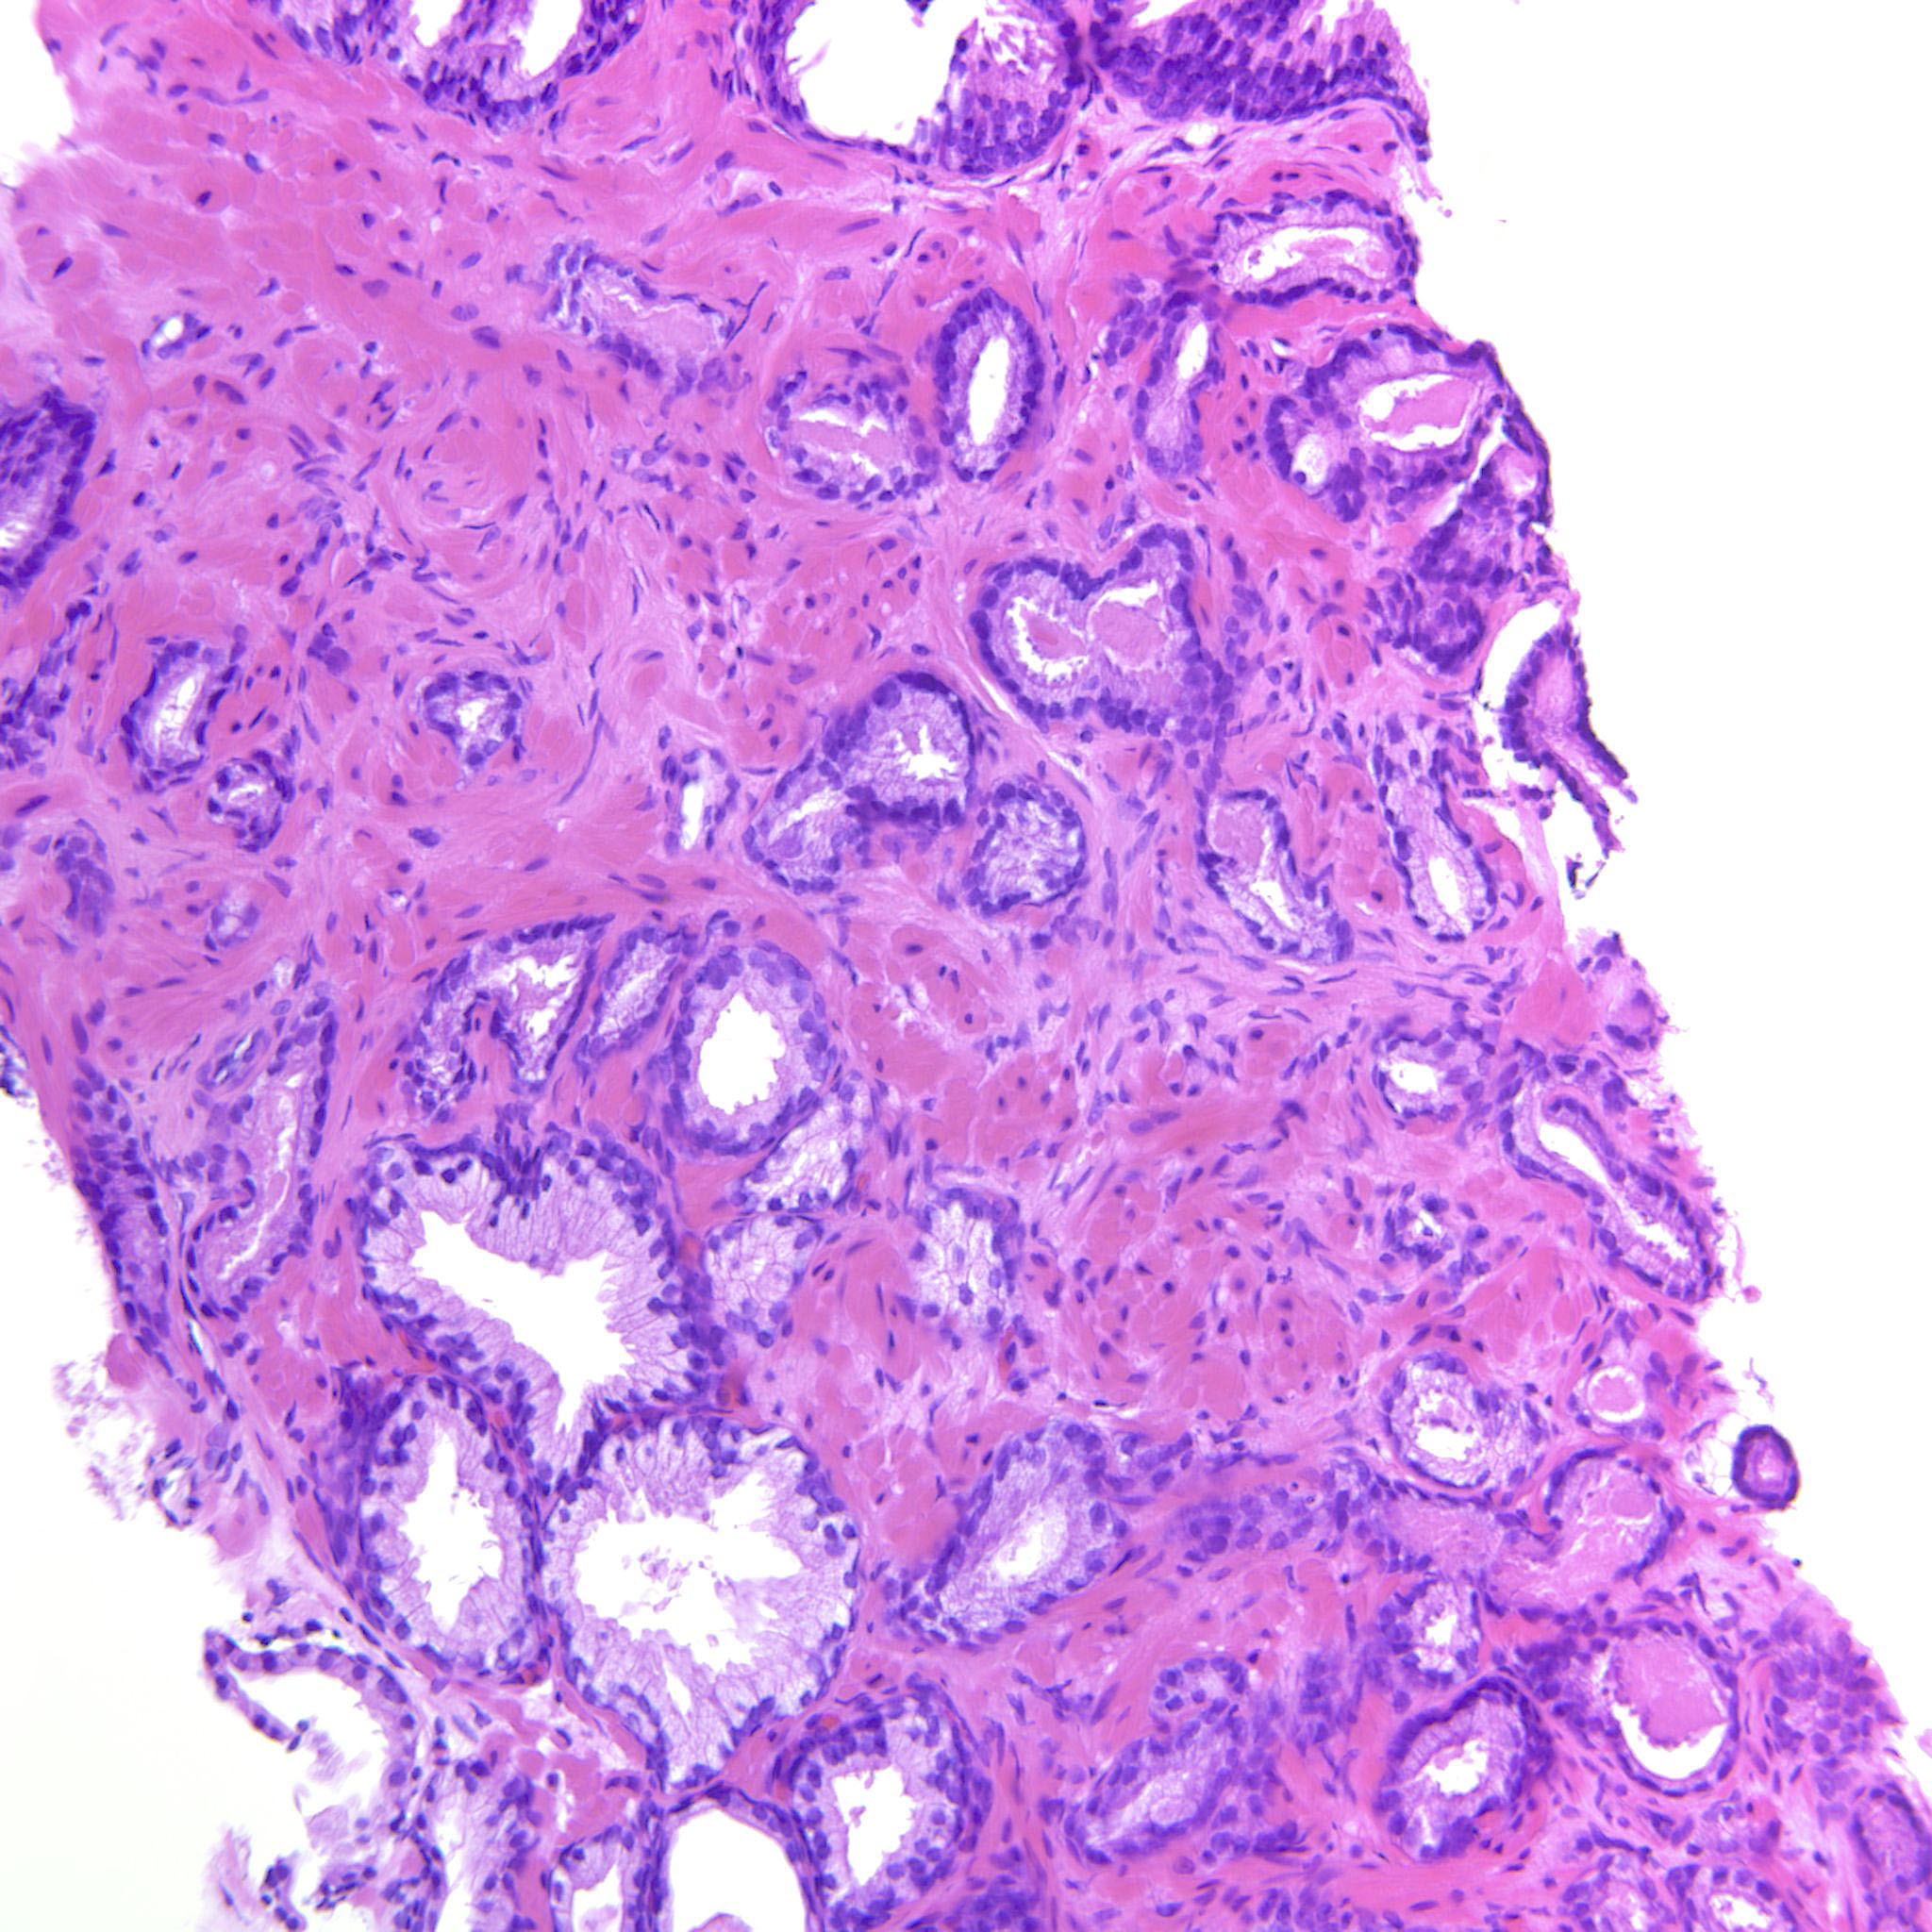

Consensus grade: GS 3+4=7 (ISUP 2)

Case description (by case creator):

Mostly GP3 but there are also a few cribriform glands.